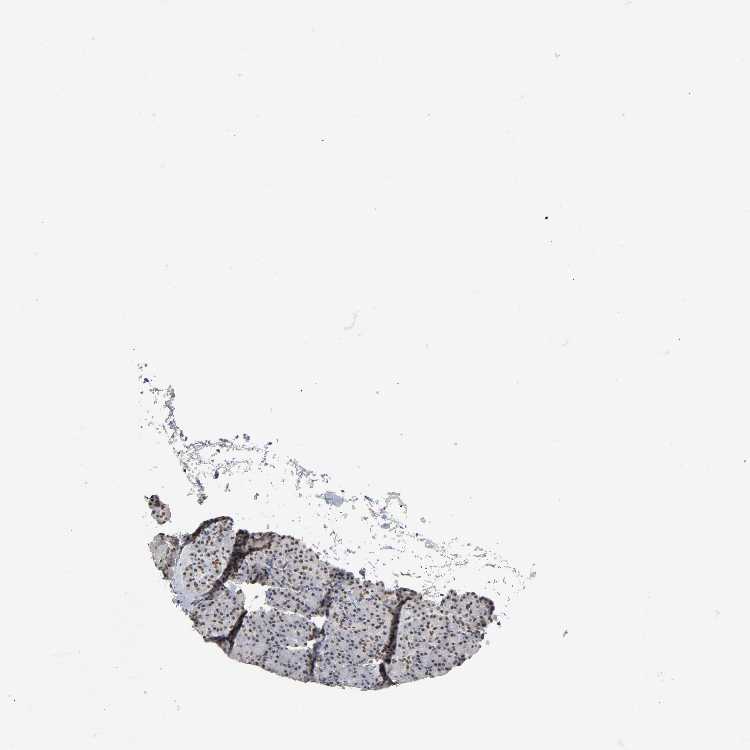

PANCREAS - Antibody stainingi

Antibody staining in the annotated cell types in the current human tissue is reported as not detected, low, medium, or high, based on conventional immunohistochemistry profiling in selected tissues. This score is based on the combination of the staining intensity and fraction of stained cells.

Each image is clickable and will lead to virtual microscopy that enables deeper exploration of all samples and also displays staining intensity scores, fraction scores and subcellular localization as well as patient and tissue information for each sample.

Antibody HPA004345

Exocrine glandular cells High

Pancreatic endocrine cells High